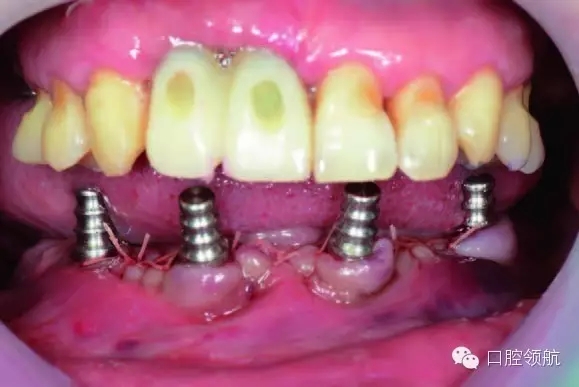

植入4顆NobelActive,后部為RP4.3*15,前部為RP4.3*13。安放閉口轉(zhuǎn)移桿(圖6-9,圖6-10)。

3.webp.jpg

圖6-9 術(shù)中拔除10顆患牙

4.webp.jpg

圖6-10 下頜植入All-on-4 后口內(nèi)照